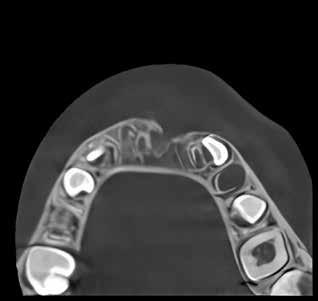

Patienttilfælde 1 (Fig. 1) er en 37-årig kvinde, henvist efter succesfuld behandling af stadie 3-parodontitis. Der er nu sundt

Før behandling

parodontium, ingen pocher over 4 mm, og både blødnings- og plakindeks er under 10 %. Patienten er motiveret for ortodontisk behandling, da hendes tænder er vandret over tid, delvist som følge af reduceret parodontium.

Der ses anterior trangstilling i begge kæber og overerupterede 1+1 og 2,1-1,2, hvilket resulterer i dybt bid med 2- tæt på ganepåbidning. Der er normale sidetandsrelationer, men der ses 5 mm horisontalt overbid (HOB) og 7 mm vertikalt

overbid (VOB). Papillen mellem 1+1 er betydeligt reduceret pga. fæstetab, og de mesialt kippede 1+1 har resulteret i en ”dark triangle”. Den facioorale funktion er for nuværende i.a. Panoramarøntgen (Fig. 1, I) viser marginalt knogletab i begge kæber og fravær af 8,7+7,8 og 8,7-8.

Objektivt anbefales behandling af det dybe bid, som ubehandlet forventes at forværres yderligere over tid. Patienten har ønske om behandling med æstetisk ortodontisk apparatur, alignere, og det vurderes muligt at behandle malokklusionen med alignere. Dog anbefales det generelt, at alignere undgås eller benyttes med væsentlige modifikationer af alignerens retention ved tandmobilitet, da dette ellers kan medføre jiggling, når aligneren tages af og på mange gange dagligt. På den anden side er der nogen evidens for, at alignerbehandling er associeret med bedre renhold og parodontal sundhed sammenlignet med fast apparatur (16).

Der planlægges alignerbehandling af begge kæber med intrusion af 1+1 og 2,1-1,2, nivellering af trangstilling UK med interproksimal reduktion (IPR) (Fig. 2 A, B) og senere IPR OK for reduktion af dark triangles mellem incisiverne efter nivellering. Patienten instrueres i at benytte alignere 20-22 timer/ dag med alignerskift hver 7. dag, og patienten ses hver 3.-8. uge under forløbet. Den første alignerserie består af 16 alignere for nivellering OK/UK og IPR i UK (Fig. 2). Efter denne serie planlægges IPR mellem incisiverne i OK for reduktion af dark triangles (Fig. 3) samt yderligere intrusion af OK og UK-fronten i 12 refinement-alignere. Patienten udviser god kooperation og er meget tilfreds med alignerapparaturet, som er mindre synligt end det faste apparatur (Fig. 4).